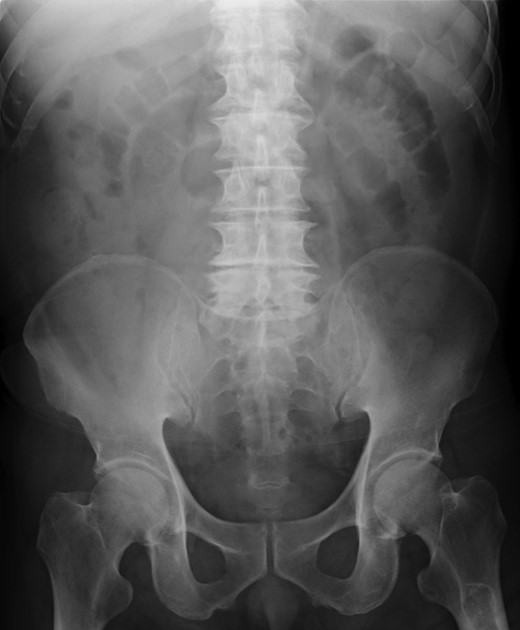

A 79-year-old man with acute abdominal pain had gone to a nearby hospital. As HPVG was detected by abdominal computed tomography (CT), he was transferred to our hospital for further examination and treatment. He had no remarkable past medical history. When he arrived at our hospital, his vital signs were relatively stable (body temperature: 37.2°C; blood pressure: 112/74 mmHg; pulse rate: 68 beats/min). However, physical examination revealed abdominal distention, rebound tenderness and abdominal guarding as signs of peritoneal irritation. The laboratory findings indicated acute inflammation (white blood cell count of 18 400/μL and Creactive protein concentration of 17.7 mg/dL), dehydration and metabolic acidosis (a level of base excess of −7.0 mmol/L). Creatine kinase was remarkably elevated (28 327 IU/L) (Table 1). Plain abdominal radiographs showed distention of the small intestine and suggested subileus (Fig. 1). Contrast-enhanced abdominal CT revealed HPVG (Fig. 2a), a contrast defect in a region of the small intestine, and a small amount of ascites around the intestine. There was no thrombus in any artery; however, the wall of the appendix was moderately thickened when we reevaluated the images retrospectively (Fig. 2b). We performed an urgent laparotomy with the diagnosis of generalized peritonitis caused by intestinal necrosis. A small amount of turbid ascites and a dilated small intestine were observed in the peritoneal cavity. Although the entirety of the small intestine and colon were explored, no intestinal ischemia was detected. Then, we found discoloration of the appendix with wall thickening. We thus made a clinical diagnosis of peritonitis caused by gangrenous appendicitis. Although the appendix wall was fragile, no macroscopic perforation of it was observed. We performed appendectomy and abdominal drainage. Based on the pathological findings, the patient was diagnosed with gangrenous appendicitis, with no evidence of malignancy (Fig. 3). Escherichia coli was positive in the ascitic culture. After the surgery, intravenous antibiotic treatment (meropenem) was administered. The patient subsequently went into septic shock with disseminated intravascular coagulation (DIC). He was therefore admitted to the intensive care unit (ICU), where he received blood purification therapy. The CT images on Day 7 after the surgery showed that HPVG had disappeared (Fig. 4). He left the ICU 7 days after the surgery and was discharged from the hospital another 10 days later.